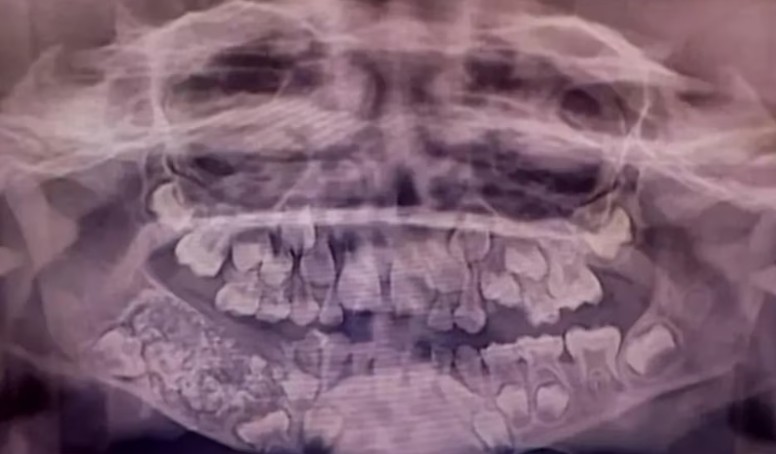

Las radiografías y tomografías computerizadas revelaron la presencia de una masa de aproximadamente 200 gramos alojada en el interior de la mandíbula. El Dr. Senthilnathan, responsable del Departamento de Cirugía Oral y Maxilofacial, identificó la anomalía como un “odontoma compuesto”, una variante benigna de tumor directamente relacionada con el desarrollo dental.

“La especie de tumor que detectamos impidió el crecimiento permanente de los molares en el niño en el lado afectado”, explicó el cirujano tras completar la operación. Las imágenes médicas mostraban numerosos dientes rudimentarios agrupados en un tejido con forma de bolsa, una presentación clínica poco frecuente en la literatura especializada.

La magnitud del descubrimiento sorprendió incluso a los médicos más experimentados. Según informó Science Alert, la bolsa contenía 526 pequeños dientes de dimensiones variables, desde apenas 0,1 milímetros hasta 15 milímetros de longitud. El proceso de clasificación y contabilización de cada pieza dental requirió cinco horas adicionales de trabajo meticuloso en el laboratorio.

La Dra. Pratibha Ramani, directora del Departamento de Patología Oral y Maxilofacial, destacó que todos los dientes extraídos presentaban las estructuras características de las piezas dentales normales: corona, raíz y recubrimiento de esmalte. “Incluso la pieza más pequeña tenía las características de un diente tradicional”, subrayó la especialista, quien enfatizó la ausencia de precedentes con tal número de dientes en los registros médicos mundiales.